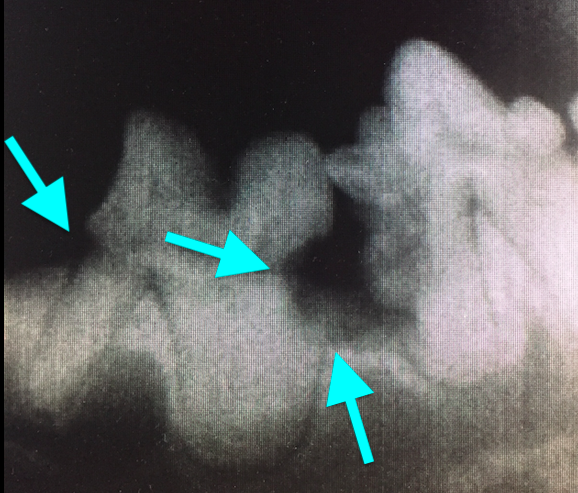

Резорбция зубов развивается вторично на фоне активности многоядерных одонтокластов, которые разрушают твердые ткани зуба. Как правило, процесс начинается в цементе на боковой поверхности корня в любом месте, а затем распространяется на дентин апикально и/или коронально.При резорбции, начинающейся на поверхности корня, в глубине альвеолы, процесс замещает периодонтальную связку и корень костно- или цементоподобной тканью. При резорбции, которая прогрессирует в сторону коронки, потеря дентина и эмали обнажает резорбцию в полости рта. Затем возникает воспаление окружающих тканей, что приводит к повышенной чувствительности. Многие невоспалительные поражения не прогрессируют – процесс остается апикальнее цементно-эмалевой границы (фото 5).

Повреждения, которые начинаются вблизи цементно-эмалевой границы, быстро подвергаются воздействию среды полости рта, где они контаминируются и воспаляются. Существует предположение о том, что эти поражения вызваны накоплением бляшек, воспалением и высвобождением цитокинов и липополисахаридов, которые стимулируют миграцию кластических клеток в эту область. Затем резорбция зуба распространяется вниз по корню, инфицируя периодонтальную связку и предотвращая замещение утраченных твердых тканей материалом, подобным кости или цементу (фото 6).